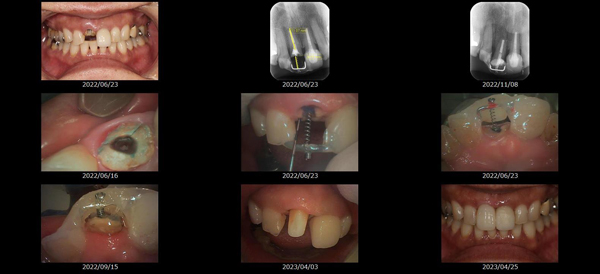

救歯MTM

虫歯が大きくて残せない歯、転倒などの事故により歯が根の深いとこで折れてしまったなどで、抜かざるを得ない歯を、骨の中に埋まっている健全な根を、骨の上に矯正的に引き上げることで、その歯を抜かず温存、救歯できる可能性のある治療方法です。

この特別な診療である救歯MTMは、以下のような特徴があります。

①健全な歯を、歯肉から見える位置にまで引き上げることで

根の治療の成功率を上げることが出来る。唾液には沢山の細菌がいます。唾液が入らない環境での根の治療を(神経の治療)を行うことで神経の治療、根の治療の成功率は格段と上がります。

②骨の上にある歯と土台で支える被せもの製作できる。

被せものを土台だけに頼ることなく、引き上げた健全な歯でも支えることで、歯への被せ物がしっかりと装着できるようになる。

③抜かずに歯を活かすことで、隣の歯を削るブリッジやインプラントにしないで済むことがある。

歯を矯正的に引き上げることで、その歯を救歯できるだけでなく、隣の歯を削るなどの侵襲を回避できる場合がある。

リスク

- > 歯を矯正的に引き上げることで、骨の中の根の長さは短くなりますが、その短さでも安定するという診断をした場合のみ施術になります。 残せる歯、根の長さが短い場合は、この救歯MTMの治療対象とならない場合がございます。

- > 治療期間が数か月~1年に及ぶ場合がある。

- > 費用が自費診療 44,000円 ~ 66,000円

- > 救歯MTMは救歯BTAセラミックと併用治療が必要な場合があります。

症例

-